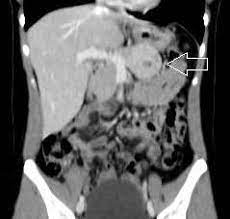

- 40% ou mais desses tumores tem componente de malignidade invasiva no tempo de seu diagnóstico;

- na tomografia ou ressonância aparecem como tumores redondos, bem encapsulados, septos grosseiros e cistos grandes, calcificações na periferia do tumor e estão mais presentes quando existe malignização (designadas de “Egg-Shell” ou casca de ovo ). São sinais de preocupação também, a presença de nódulos intracísticos, obstrução biliar, invasão de gordura peri-pancreática e ascite;

- na colangiopancreatografia não há comunicação do cisto com Ducto de Wirsung;

- a Eco-Endoscopia com bíopsia e aspirado do liquido mostra rico em mucina (muco assim como as células, pode conter atipias) e tem valores altos de marcadores como CEA, CA 19,9 (abaixo de 37,0) com níveis baixos de amilase.